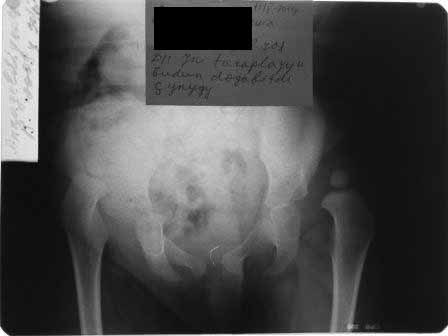

раскажу о технике закрытого вправления у детей, особенно при высоких вывихах. до 3 -х лет мы применяем лейкопластырное, крайне редко скелетное вытяжение, наложив лейкопластыри на конечности, ноги ребенка вертикально подвешивается, дале постепенно в течении 14 дней ноги разводятся в стороны при этом, поверхность кровати поднимается вверх(разведение ног быстрее до 3-4 дней), масса груза до 25 процентов тела, но крайне важно, что бы при подвешивании ягодицы (попа ребенка) были немного на весу. через 2 недели при не высоких вывихах без наркоза по лоренцу ручное вправление, при высоких вывихах под наркозом и часто сочетается подкожной миотомией аддукторов бедра, ручное вправление. вот пример девочка 2 лет

на приведенных снимках не грудной ребенок, для другого примера девочка 3 лет при поступлении в отделение на снимке супра и латеропозиция головки бедра слева. Вытяжение 2 недели, Подкожная миотомия аддукторов бедра и ручное вправление под наркозом. фиксация в гаипсе окола полугода далее на шине распорке типа Виленского.